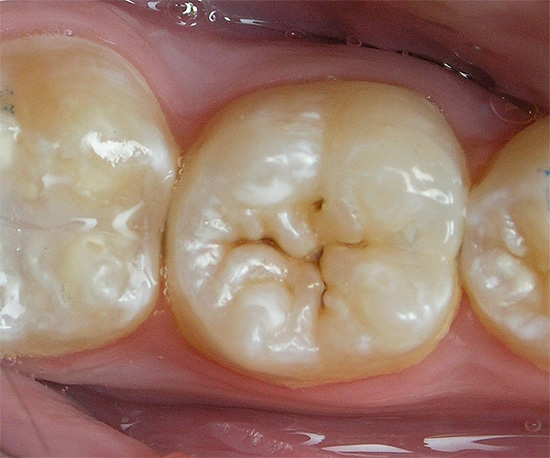

su fase iniziale della carie Questo processo di demineralizzazione avviene solo all'interno dello strato di smalto del sottosuolo. Di conseguenza, a seguito della lisciviazione attiva dei minerali e del loro lento ritorno, si forma un punto cariato. Può essere bianco o pigmentato a causa della colorazione dei "vuoti" dello smalto con coloranti e bevande.

La carie non è ancora carie. In questa fase, i cambiamenti patologici sulla superficie del dente sono ancora reversibili se le misure vengono prese in tempo.

Tuttavia, se si osserva lo stadio del danno allo smalto nelle prime fasi, si verifica un processo già irreversibile: la carie della dentina. In questa fase, i componenti minerali vengono già lavati dalla dentina stessa, che, come ricorderete, è la base del dente.